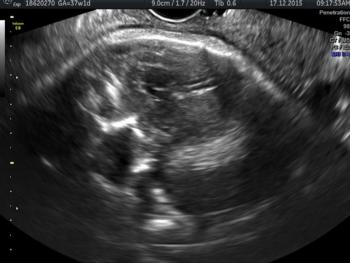

In a third study, ultrasound and fetal MRI were performed on pregnant patients with Zika virus infection at different gestational ages. Once the babies were born, they underwent ultrasound, CT and MRI. The researchers then created 3-D virtual and physical models of the skulls. More than half the babies had microcephaly, brain calcifications and loss of brain tissue volume, along with other structural changes.

"The emergence of Zika virus in the Americas has coincided with increased reports of babies born with microcephaly," said study author Heron Werner Jr., M.D., Ph.D., from the Department of Radiology at Clínica de Diagnóstico por Imagem. "An early diagnosis may help in treating these babies after birth. Moreover, the knowledge of abnormalities present in the central nervous system may give hints about the pathophysiology of the disease."